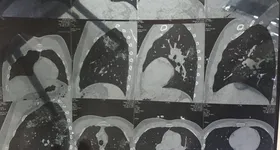

”În urmă cu trei zile, medicii au descoperit că am pete albe pe plămâni şi au decis să mă opereze de urgenţă. M-au operat pentru a-mi lua probă pentru biopsie, necesară să vadă dacă am cancer.

Intervenţia a durat mai multe ore. Sunt foarte speriat, însă pozitiv. Intervenţia are loc în Beirut. Voi fi operat de trei medici din Franţa, profesori la un spital de aici, căci avem doctori foarte buni în Beirut. Tata a fost cel care s-a ocupat de punerea la punct a intervenţiei şi găsirea lor”, a declarat Peter Kai, fostul iubit al Margheritei de la Clejani, pentru Cancan.ro, site-ul nr. 1 din România.

După intervenţia suferită la plămâni, fostul iubit al Margheritei de la Clejani a spus că medicii se arată optimişti cu privire la diagnostic: ”Mă simt rău, însă partea bună este că medicii spun că nu ar fi cancer. Biopsia a fost trimisă în Franţa şi voi primi un răspuns sigur peste zece zile”.